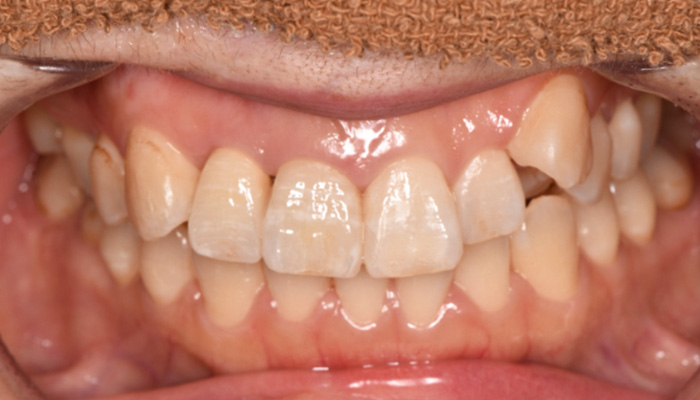

【40代女性】前歯のインプラント症例

「根が折れてしまった歯を

インプラントにしたい」

治療前

治療中

治療後

津田先生からのコメント

前歯のインプラントで特に審美的に要求の高い患者様でしたので、当院で最も信頼性の高いインプラント治療プランをご選択いただきました。また、前歯の左右差をコンポジットレジン(CR)修復治療で整えました。

| 主訴 | 根が折れてしまった歯をインプラントにしたい。 合わせて前歯の左右差を治したい。 |

|---|---|

| 治療期間 | 約4ヶ月 |

| 治療費 | 1本あたり550,000円(税別) |

| 治療内容 | 前歯のインプラント治療 |

| 治療のリスク | 前歯のインプラント治療では、審美性の問題や骨密度不足によるインプラントの不安定、神経損傷や感染のリスクがあり、術後の腫れや痛みも発生する可能性があります。 |